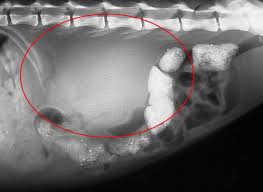

Feline kidney cancer is rare. Of the cancers that do develop in the kidneys lymphoma is the most common type to appear followed by renal cell carcinoma. Cats love routine so try to stick to a consistent feeding sleeping.

Like other adenocarcinomas adenocarcinoma of the kidney is very aggressive growing rapidly and metastasizing to other parts and organs of the body. Your cat might benefit from dialysis if you afford it. Rare condition is cats that is usually associated with feline leukemia virus which is usually identified as the cause. This is not a common type of tumor in.